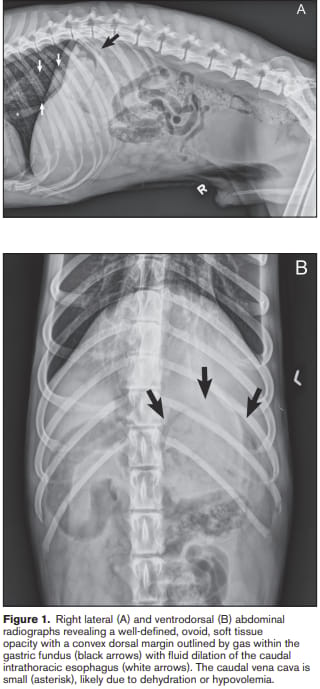

Figure 1. Right lateral (A) and ventrodorsal (B) abdominal

radiographs revealing a well-defined, ovoid, soft tissue

opacity with a convex dorsal margin outlined by gas within the

gastric fundus (black arrows) with fluid dilation of the caudal

intrathoracic esophagus (white arrows). The caudal vena cava is

small (asterisk), likely due to dehydration or hypovolemia.